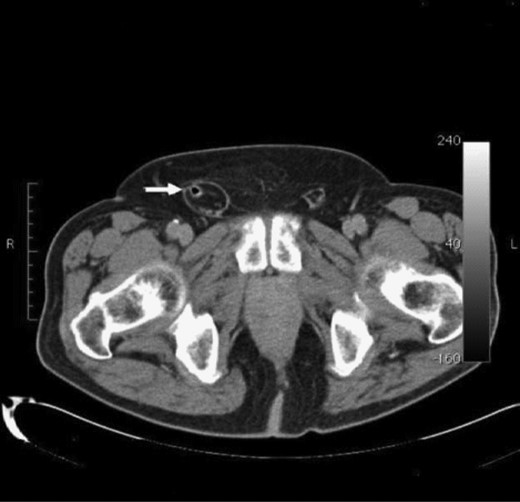

A 71-year-old male arrived at our hospital with severe abdominal pain and two episodes of dark, bloody emesis. He was afebrile, with vitals within normal limits. His medical history included hypertension, diabetes mellitus, hyperlipidemia, cerebrovascular accident, coronary artery disease, peptic ulcer disease, depression and substance abuse, and he had been compliant with his medical treatments. Surgical history was significant for a hand surgery years prior. He had no allergies and family history was non-contributory. He endorsed constipation for 2–3 days and localized severe periumbilical pain. A non-reducible right groin mass with severe tenderness to palpation was noted on physical exam. A CT scan with oral enhancing contrast of the abdomen and pelvis showed right inguinal hernia with an incarcerated, inflamed vermiform appendix and obstructing fecalith (Fig. 1). A preoperative diagnosis of an Amyand's hernia was made and the patient was prepared for surgery.

CT scan of a right inguinal hernia with incarcerated, inflamed vermiform appendix and an obstructing fecalith.